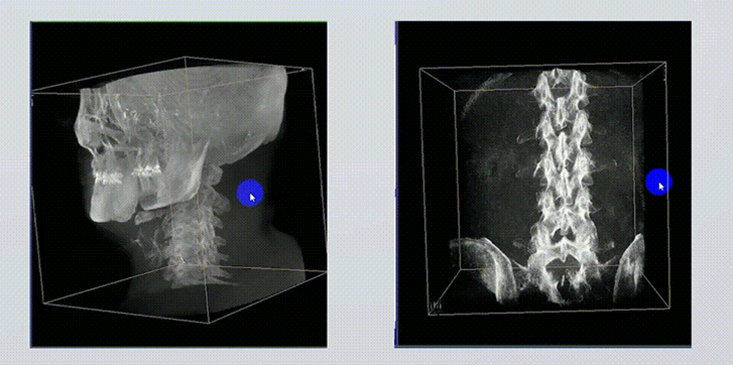

1、術(shù)中實(shí)時(shí)三維成像

術(shù)中三維成像和橫斷面圖像提供多角度的手術(shù)診斷信息,輔助醫(yī)生進(jìn)行術(shù)中評估判斷,諸如骨折復(fù)位情況和內(nèi)植入螺釘?shù)某叽绾臀恢?,輔助手術(shù)更好地完成。

提供更大的術(shù)中三維成像視野,采集更多圖像信息,可一次拍全全段頸椎、全段腰椎、七節(jié)胸椎、雙側(cè)骶髂關(guān)節(jié)、股骨頭及單側(cè)盆骨。